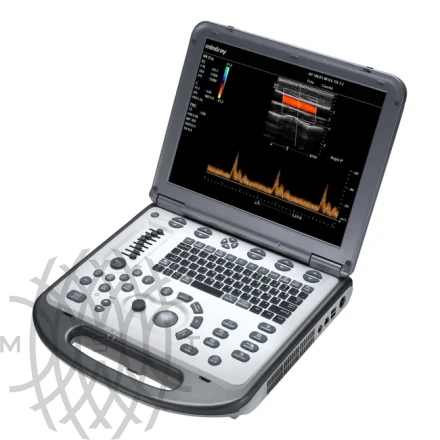

УЗИ аппарат Mindray M6 портативный

Характеристики

- M6 основной блок

- 15" монитор высокого разрешения

- Режимы сканирования:B/M/CFM/PDI/Направленный PDI/PW/Цветной M-режим

- Импульсно-волновой допплер PW (включая режим высокой частоты повторения импульсов HPRF)

- iBeam™ - многолучевое сложносоставное сканирование

- iClear™ - адаптивный алгоритм подавления зернистости

- PSH™ - Гармоника с фазовой инверсией

- iTouch™ - автоматическая оптимизация изображений

- iZoom™ - увеличение изображения во весь экран

- HR Flow - Режим отображения кровотока с высоким пространственным разрешением

- iScanhelper -Встроенный атлас ультразвуковых исследований

- 1T твердотельный жесткий диск и База данных пациентов iStation™

- Разъем S-Video и 2.0 USB порты

- Блок питания и литий-ионная батарея

- Кейс (чемодан) для транспортировки